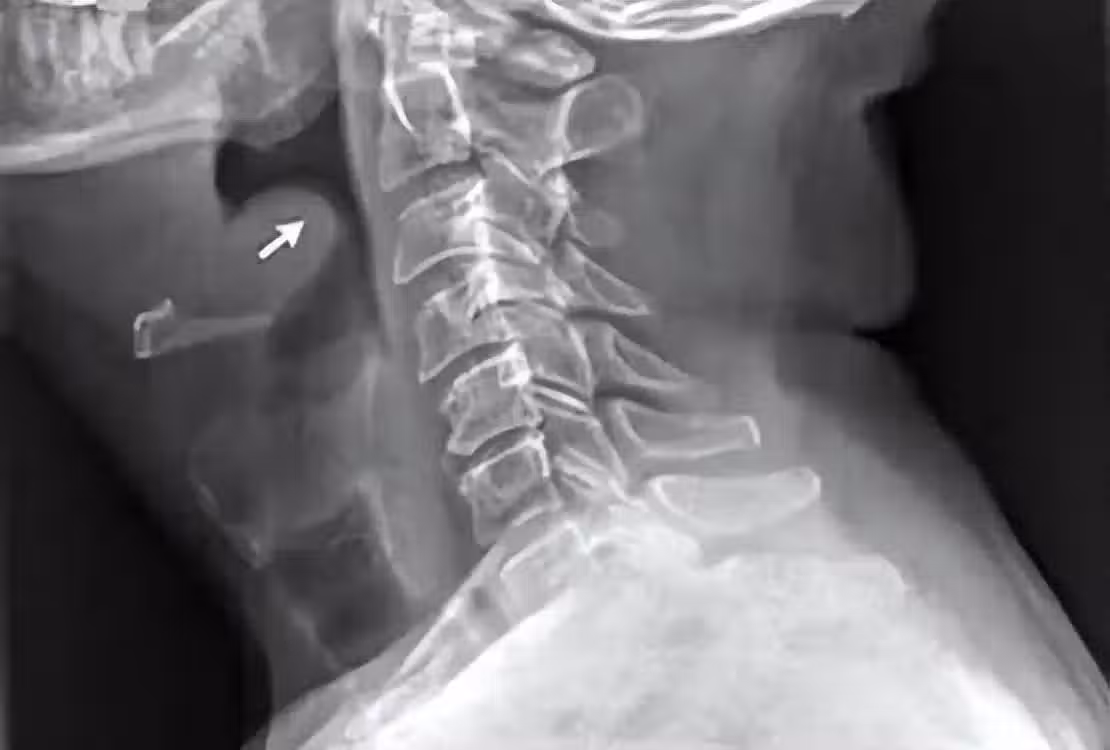

按照患者生前的經歷推測,她可能是前一天晚上吃火鍋時,因為高溫和辛辣刺激等,導致會厭出現了炎症水腫。再加上冷飲的刺激,會厭水腫進一步加劇。由於症狀一開始和普通的咽炎、咽痛十分相似,患者沒有重視,最終窒息死亡。

也就是說,患者是被活活憋死的。